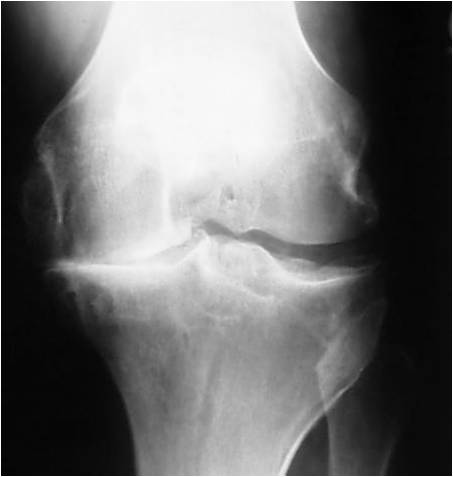

Arthritic Knee

All joints have a smooth white slippery covering called cartilage which acts as the bearing surface for movement. It is where the “rubber hits the road” for the movement of joints. There are over 100 various disorders which cause damage to the cartilage. The most common arthritis, osteoarthritis, results from stresses on cartilage that are greater than the tissue can withstand. This can be routine forces on weakened cartilage or from excess forces on normal cartilage. Researchers have found that an inherited weakness of the main protein in cartilage (collagen) frequently leads to early osteoarthritis. Hormones that help make women’s tissues soft, supple and more flexible for pregnancy may be a reason women have twice the osteoarthritis of men. It is easy to understand how the forces of direct trauma can damage cartilage and its underlying bone. Motor vehicle accidents, falls or severe sports injuries, especially those that tear ligaments, are well known causes of arthritis later in life. Using a tire example, driving recklessly over potholes or across sharp metal objects will clearly tear up your tires! Excess force on the joint over the long term can also wear out healthy cartilage.

People with crooked legs from bowlegs or knock-knees or from poorly healed fractures of the leg bones, wear out their cartilage on the high stress side of their joints. People with straight legs can also overload their cartilage with continuous loads that crush their cartilage. Participation in high level sports like soccer and football has also been associated with more frequent arthritis of the hip and knee. Occupations where heavy loads are lifted repeatedly, such as farming and ranching, can also lead to arthritis. Being overweight causes heavy loads across your joints with every step. Obesity is not only a common cause of hip, knee, and ankle arthritis, but it also makes your symptoms worse.